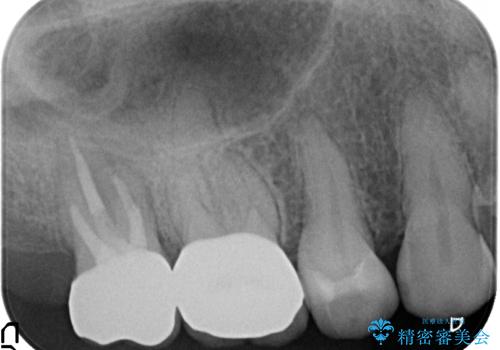

- 右上6、7の詰め物、被せ物を治して欲しいといらっしゃった方の症例です。

右上6は虫歯を除去し、右上7は再根管治療後、オールセラミッククラウンによる補綴を行いました。

- 根管治療により痛みや腫れがひかない事や、術後に痛みや腫れが生じる事、治療によるファイル破折やパーフォレーションなどの偶発症、術後の歯根破折を生じる可能性もあります